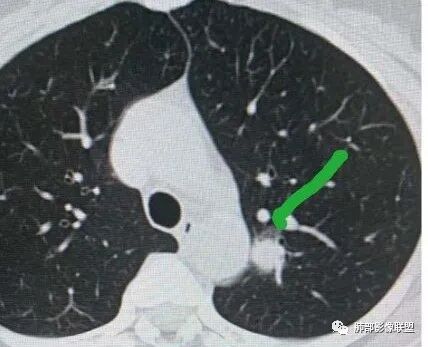

一、先讨论GGN吧

1、密度?MGGN?PGGN?

2、边界?清?不清?

3、有无收缩力?有胸膜牵拉?毛刺?

4、血管连通 移动:3型?4型?

两条都进入,相互交通-4

常规判断还需要大小、CT值

大家诊断啥?

为啥不是原位?

有收缩,牵拉

血管进入增粗,胸膜牵拉

有月牙 两条都进入,相互交通-4 胸膜牵拉

不是纯的GGO

血管进入

二.左肺上叶前段磨玻璃结节:

该结节较大,边界清楚,小叶间隔阻挡特征相当明显,微浸润腺癌的诊断几乎没有争议!